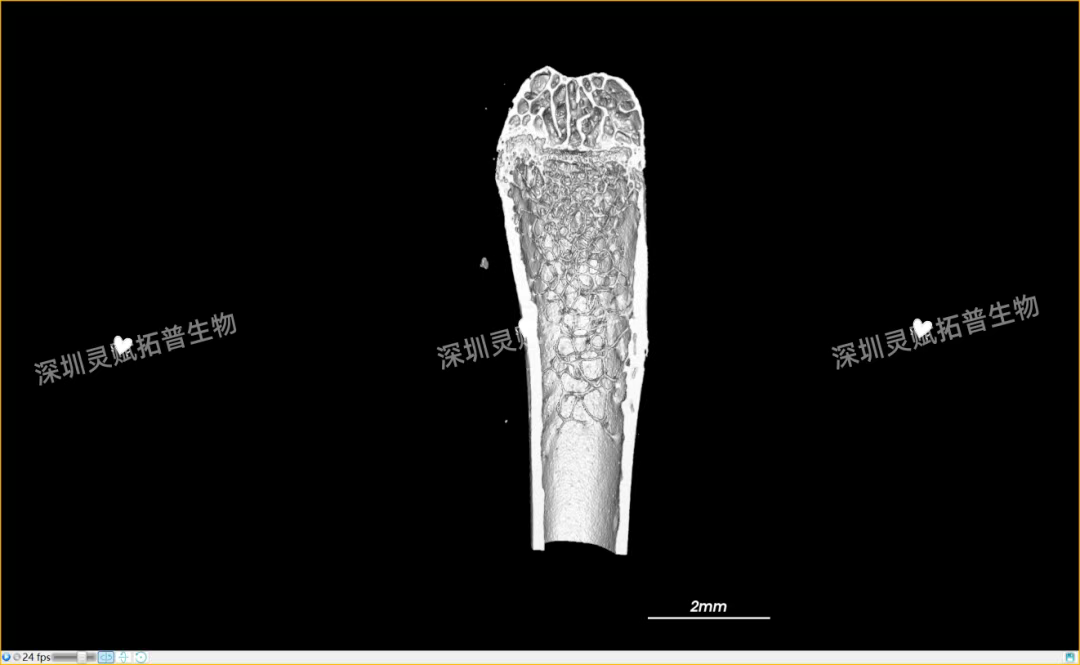

以小鼠股骨检测为代表,带大家直观感受九州ku游官网生物的服务实力:

本次实验对 E2 系列(E2-1、E2-2、E2-3)共3个小鼠股骨样本进行标准化扫描,取得了 0.5mm、2mm 等不同尺度的清晰成像,不仅直观呈现了股骨的宏观形态,更精准捕捉到骨小梁排列、皮质骨厚度等微观细节,为后续骨质疏松、骨修复等相关研究给予了可靠的量化数据支撑。

下附E2系列的典型案例:小鼠股骨扫描成像图